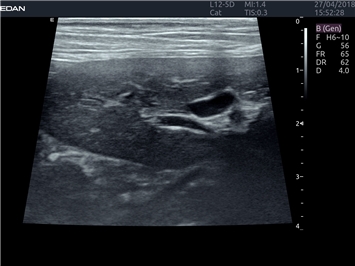

EDAN Acclarix LX4 VET

Расширьте свои представления. Когда речь заходит о стабильности, производительности и эффективности, существует одна ультразвуковая система, которая расширяет возможности ветеринарных исследований.

EDAN Acclarix LX4 VET представляет собой профессиональную ультразвуковую систему, специально разработанную для ветеринарных исследований. Сочетание стабильности, высокой производительности и эффективности делает эту систему идеальным выбором для современной ветеринарной практики.

• Мультилучевое сложно-составное сканирование (SCI):

• Повышенная четкость изображения

• Улучшенная визуализация сложных анатомических структур